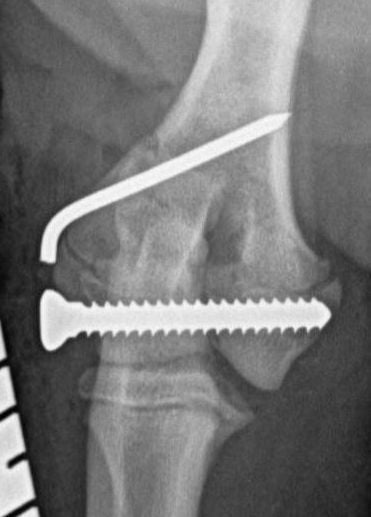

Traditionally, humeral unicondylar (lateral or medial) fractures have been managed with internal fixation using a transcondylar bone screw and an anti-rotational device. This is generally a Kirschner wire (K-wire) or Steinmann pin (Figure 1), which is placed across the epicondylar ridge component of the fracture (Bojrab, 1975; Denny and Butterworth, 2000; Jackson, 1983; Olmstead, 1993). However, reports of complications relating to mechanical failure due to implant migration in a series of patients varying widely in age and breed concluded that using a supracondylar K-wire is more likely to cause major complications than using an epicondylar bone plate (Perry et al., 2015; Sanchez Villamil et al., 2019). This conclusion was endorsed by an in vitro study that showed that stiffness, yield load and load to failure are all greater when bone plates, rather than K-wires, are used in conjunction with a transcondylar bone screw to stabilise humeral unicondylar fractures (Coggleshall et al., 2017).

These concerns have led to recommendations being altered over the past decade or so, with veterinarians now using bone plates, instead of K-wires, as an adjunct to a transcondylar screw when managing humeral unicondylar fractures (Figure 2), even in puppies (Figure 3) (Clark, 2016; Kvale et al., 2022). However, the basis on which this conclusion for puppies was reached appears to have been flawed because it assumed that what had been shown to be the case for adults would also apply to immature patients. As the conclusion was felt to conflict with the author’s experience of treating such patients, a retrospective study was undertaken to evaluate complications and outcomes in immature dogs treated for humeral unicondylar fractures at one centre over a 10-year period (Butterworth, 2022). The findings of this study are summarised in this article.